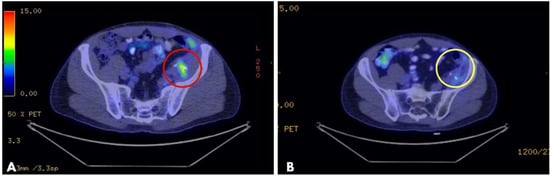

- Ottlakan, A.; Lazar, G.; Hideghety, K.; Koszo, R.L.; Deak, B.; Nagy, A.; Besenyi, Z.; Bottyan, K.; Vass, G.Z.; Olah, J.; et al. Clinical considerations of bleomycin based electrochemotherapy with variable electrode geometry electrodes for inoperable, deep-seated soft tissue sarcomas. Bioelectrochemistry 2022, 148, 108220. [Google Scholar] [CrossRef]

- Simioni, A.; Valpione, S.; Granziera, E.; Rossi, C.R.; Cavallin, F.; Spina, R.; Sieni, E.; Aliberti, C.; Stramare, R.; Campana, L.G. Ablation of soft tissue tumours by long needle variable electrode-geometry electrochemotherapy: Final report from a single-arm, single-centre phase-2 study. Sci. Rep. 2020, 10, 2291. [Google Scholar] [CrossRef] [PubMed]